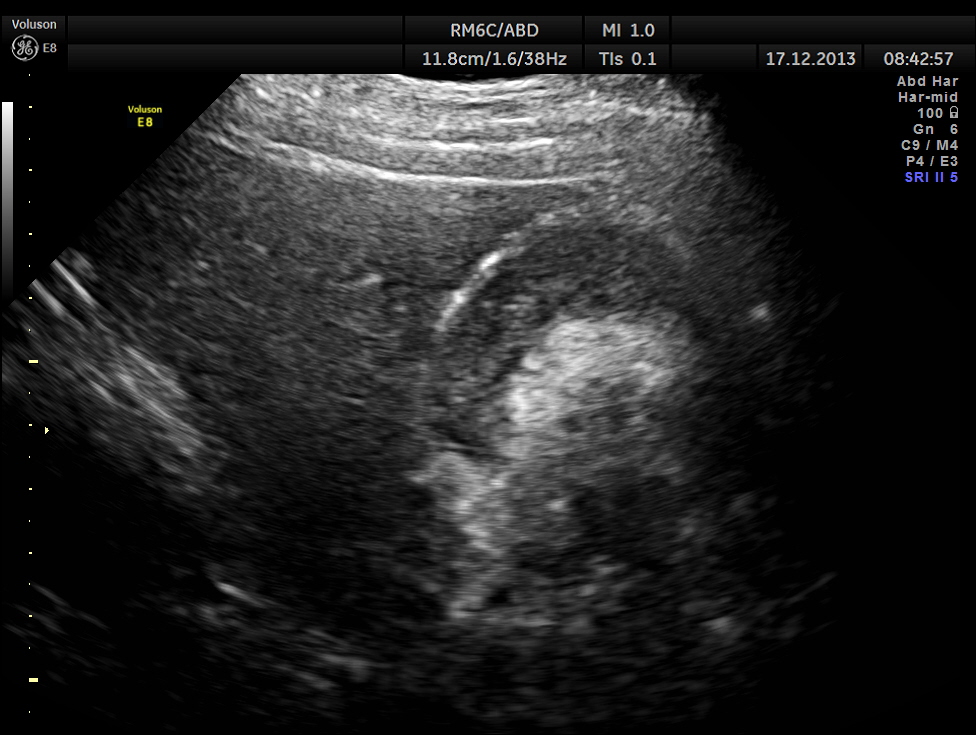

ACUTE CHOLECYSTITIS WITH MULTIPLE SMALL GALLSTONES AND ECHOGENIC SLUDGE WAS SEEN.

A high definition live rendering is given below.

The pancreas appeared to be normal.